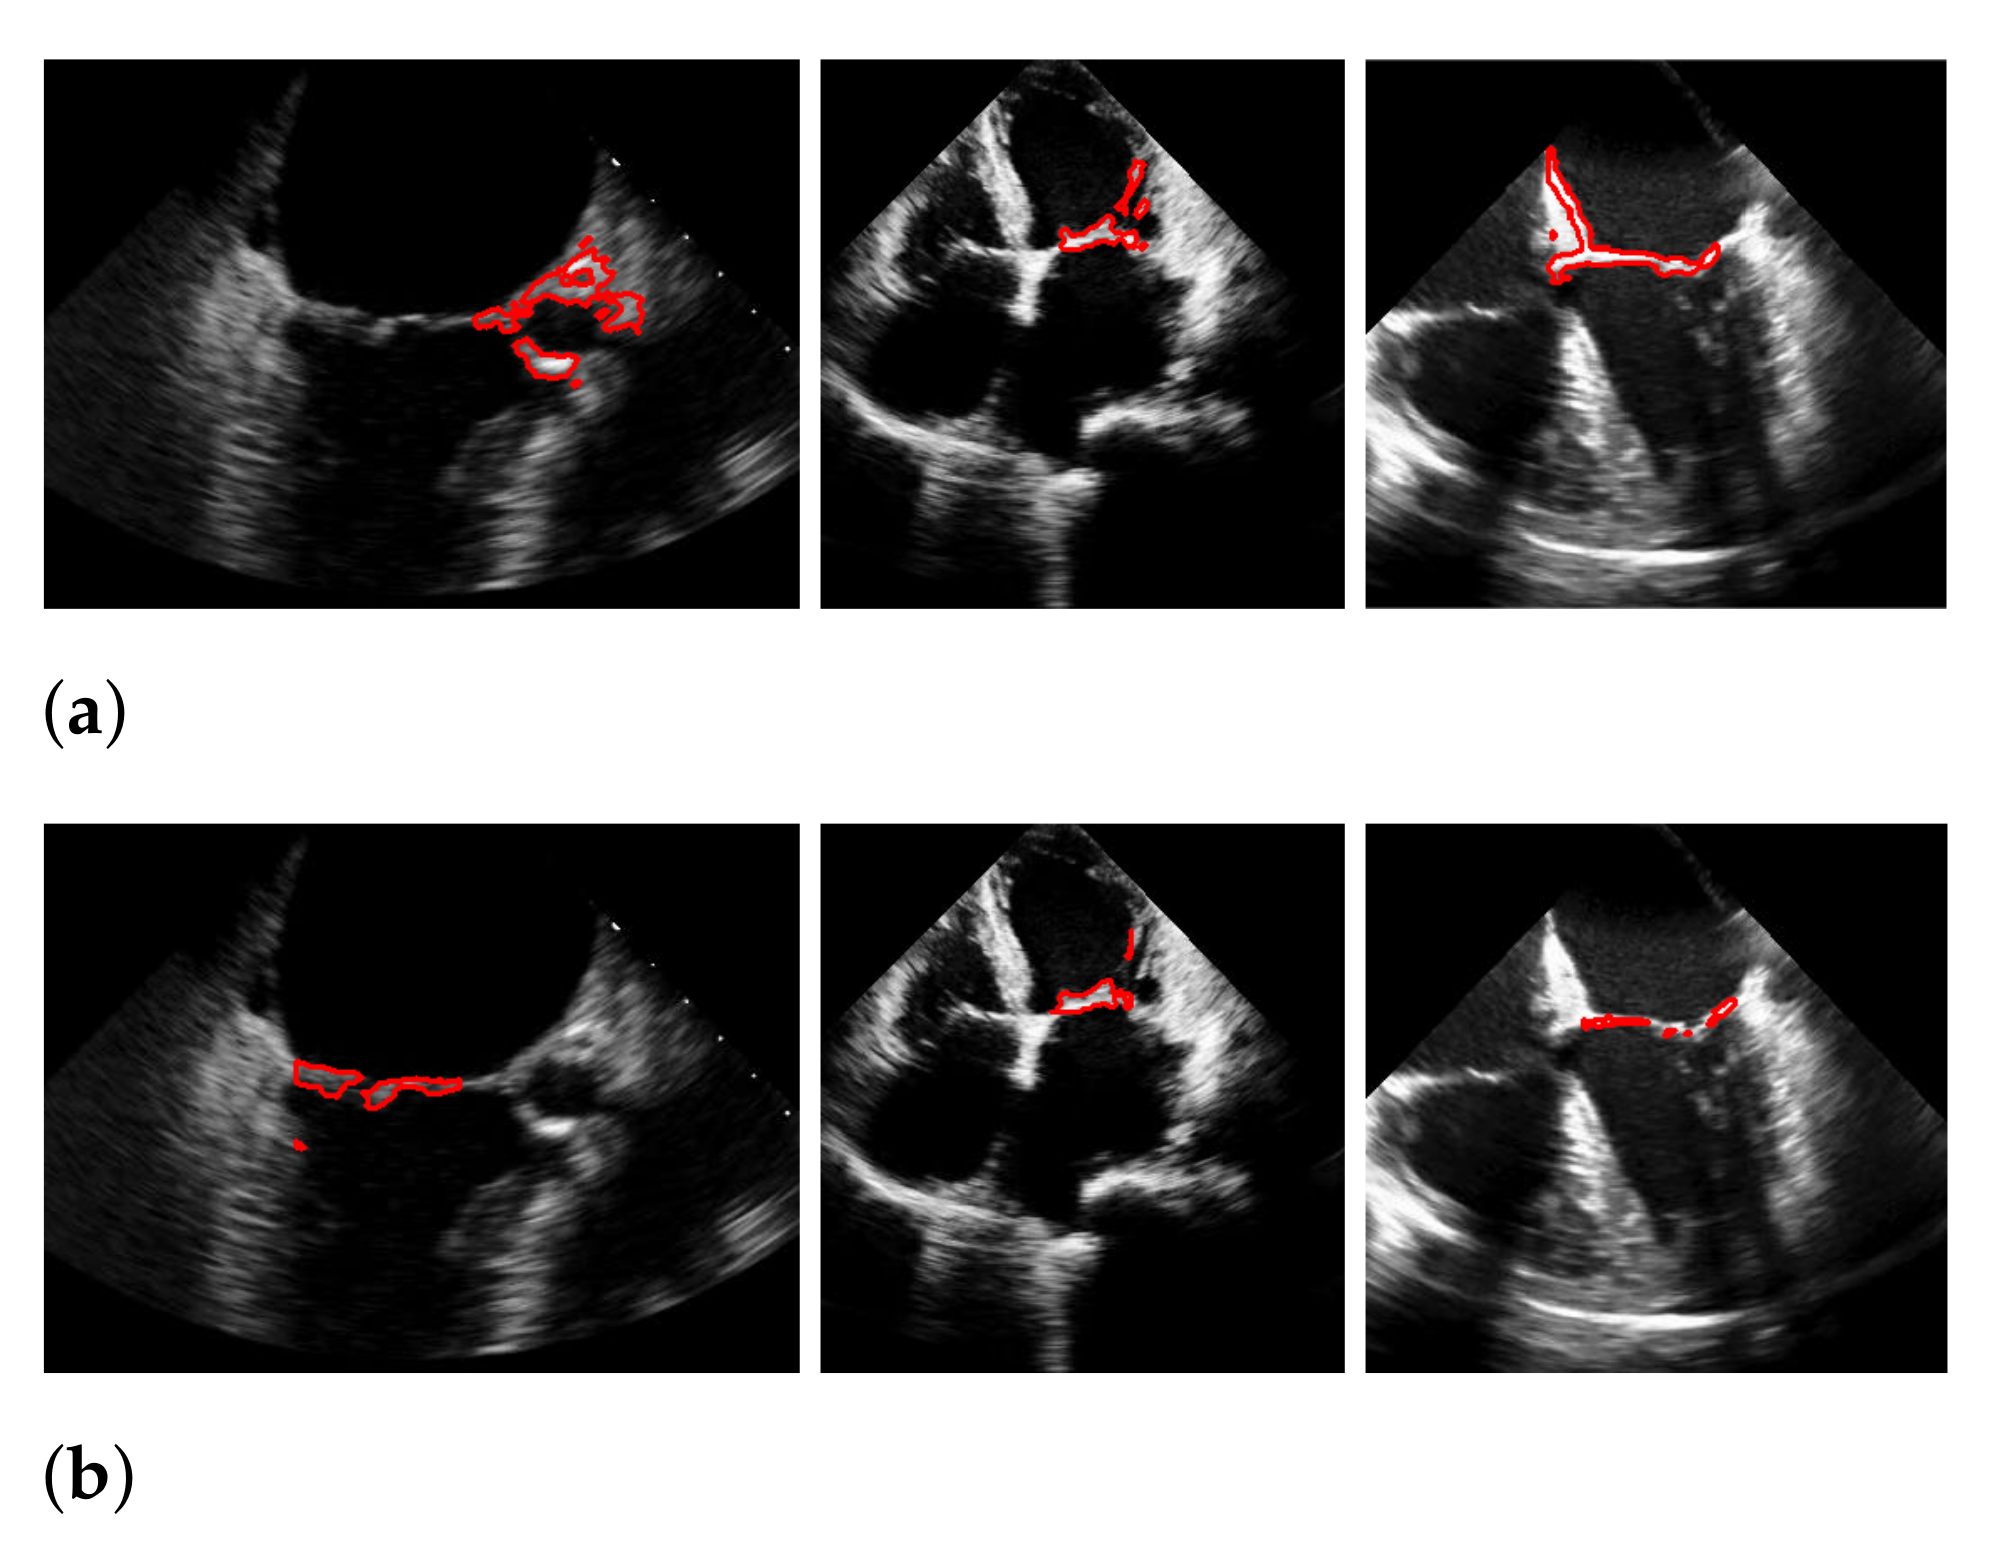

Figure 17.

Best (a), worst (b) and an average (c) detection and segmentation result in terms of the recall and f1-score. The green contour indicates the ground truth segmentation, the red contour indicates the detected window location and the calculated segmentation.

The bottom rows show the result on a video, including the mitral valve and the aortic valve on the left, which is also segmented. Since the final segmentation accuracy strongly depends on the windowing result the best/worst f1-score of the segmentation with windowing and the best/worst recall value of the windowing method on our evaluation dataset refer to the same videos as expected. These are shown in Figure 17. Here, the first row shows the best result and the second row, the worst. The latter is, again, caused by the second valve on left, which is also moving fast. The last row shows an average result of the mitral valve detection and segmentation.

During our experiments, we observed different kinds of failures in the segmentation with windowing, which we illustrated in Figure 19 with three example frames. The most far-reaching failure, which appears in the form of a very low f1-score, is the complete missing of the mitral valve during windowing, as shown in the upper left image, and can occur in methods with windowing, as here in the method of Corinzia et al. [40]. The two images in the middle show failures that can occur due to the rectangular shape of the windows, where in some frames, parts of the heart muscle are segmented, as it is located in the area of the window during the contraction of the heart. The third type of failure is a slightly shifted window, as seen in the upper right image, which can occur when one valve leaflet stands out, due to strong pixel intensity and strong surrounding muscle movement in contrast to the other leaflet as well as when a second valve near the mitral valve appears in the video. This failure can also be seen in Figure 17 in the middle image in our worst result. Failures, which can occur in our method, due to too strong regularization of or in (8), are partially too narrow, perforated segmentations as shown in the lower right image. Here, the valve is correctly localized, but is not completely captured in some frames of the video.